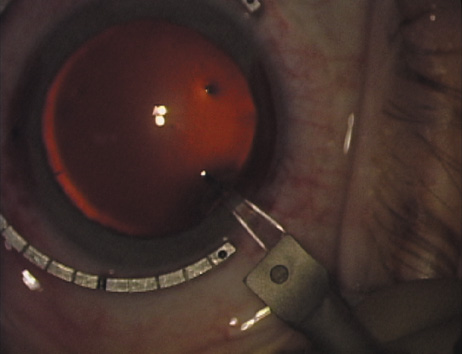

Case 2 is a 79-year-old woman who presented with a very dense left cataract. Her refraction was recorded at −2.25 +2.75 × 125 with a difficult end point. Her manual keratometry and topography measurements were consistent and revealed slightly less than 1.75 D at 120 degrees. Because of the questionable refraction, greater value was placed on the corneal measurements. Based upon the cataract nomogram, the plan was for paired LRIs of 40 degrees to be placed over the steep 120-degree axis (Figs. 1219).

Fig. 19. The temporal single-plane clear corneal incision is placed independent of the LRIs. (Reprinted from Hardten DR, Lindstrom RL, Davis EA. Phakic Intraocular Lenses: Principles and Practice. Thorofare, NJ: SLACK Incorporated, 2004, with permission.)